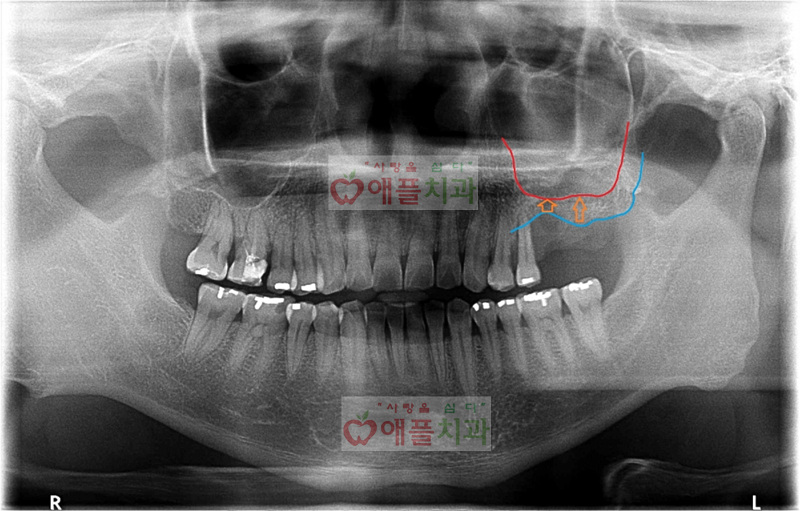

<처음 내원시>

얼마전 좌측 상악 어금니 두개치아를 발치하셨고, 임플란트 상담위해 병원에 찾아주신 환자분이십니다.

예전에 좌측 상악 임플란트 식립을 위해서는 상악동 골이식(=상악동 거상술)이 필요하다는 설명을 들으셨고, 상악동 골이식이 어렵고 난이도가 높은 수술인 만큼 저희병원을 찾아주시고 믿고 시술을 진행하셨습니다.